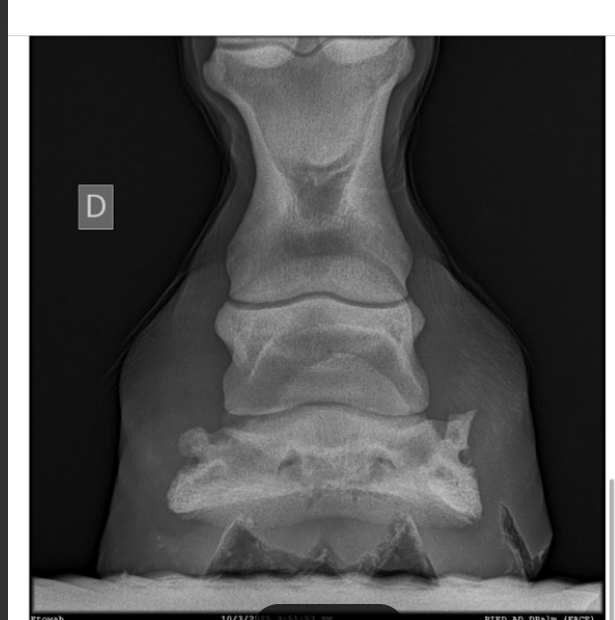

C’est un antérieur droit, pris de face. On voit qu’il y a un déséquilibre latero médial et que le cartilage est affiné en interne. Si on mesure la distance de P3 au sol, on dirait que P3 est plus haute en externe, mais du coup je ne comprends pas pourquoi c’est le côté interne qui est pincé.

La vétérinaire était pas capable de me dire ce qu’il fallait faire en parage, de quel côté il fallait rabaisser. Le talon interne a tendance à être plus haut, donc si je suis mes repères habituel, c’est celui ci que je dois légèrement baissé, mais je ne trouve pas cela logique avec la radio.